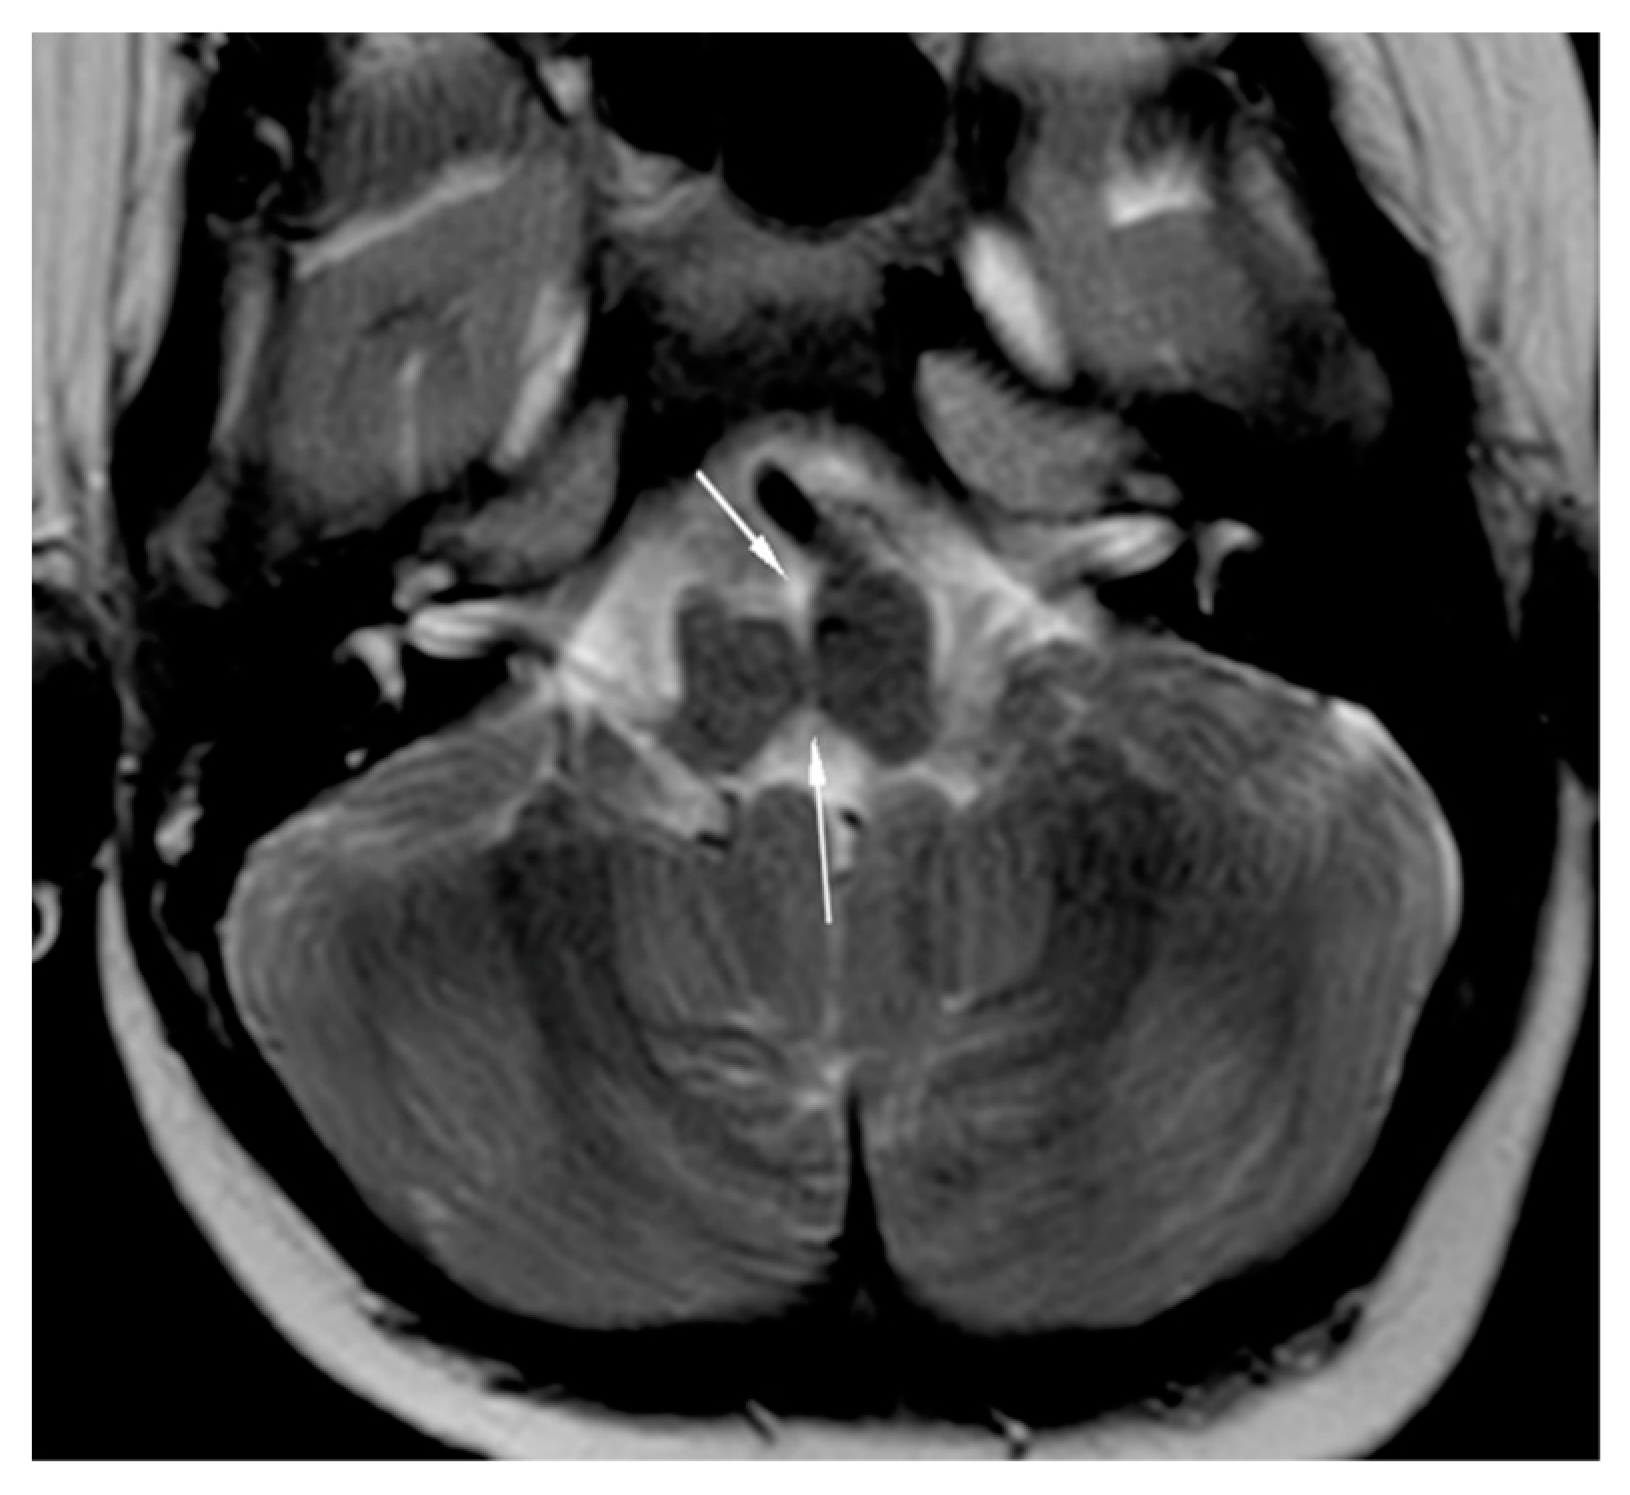

Brain magnetic resonance imaging (MRI) demonstrated hypoplasia of the brainstem (Figure 2), a left thalamus volume larger than the right (Figure 3), an enlarged fourth ventricle, an anterior and posterior midline bulbar and pontine cleft (split-pons sign) (Figure 4), a butterfly configuration of the medulla (Figure 5), an occipital and parietal plagiocephaly on the right side, and a slight benign enlargement of the subarachnoid spaces in the frontotemporal area. There were no signal changes within the medulla or pons in any of the brain MRI sequences.

Figure 4. MRI brain axial T2-weighted image showing split pons sign.